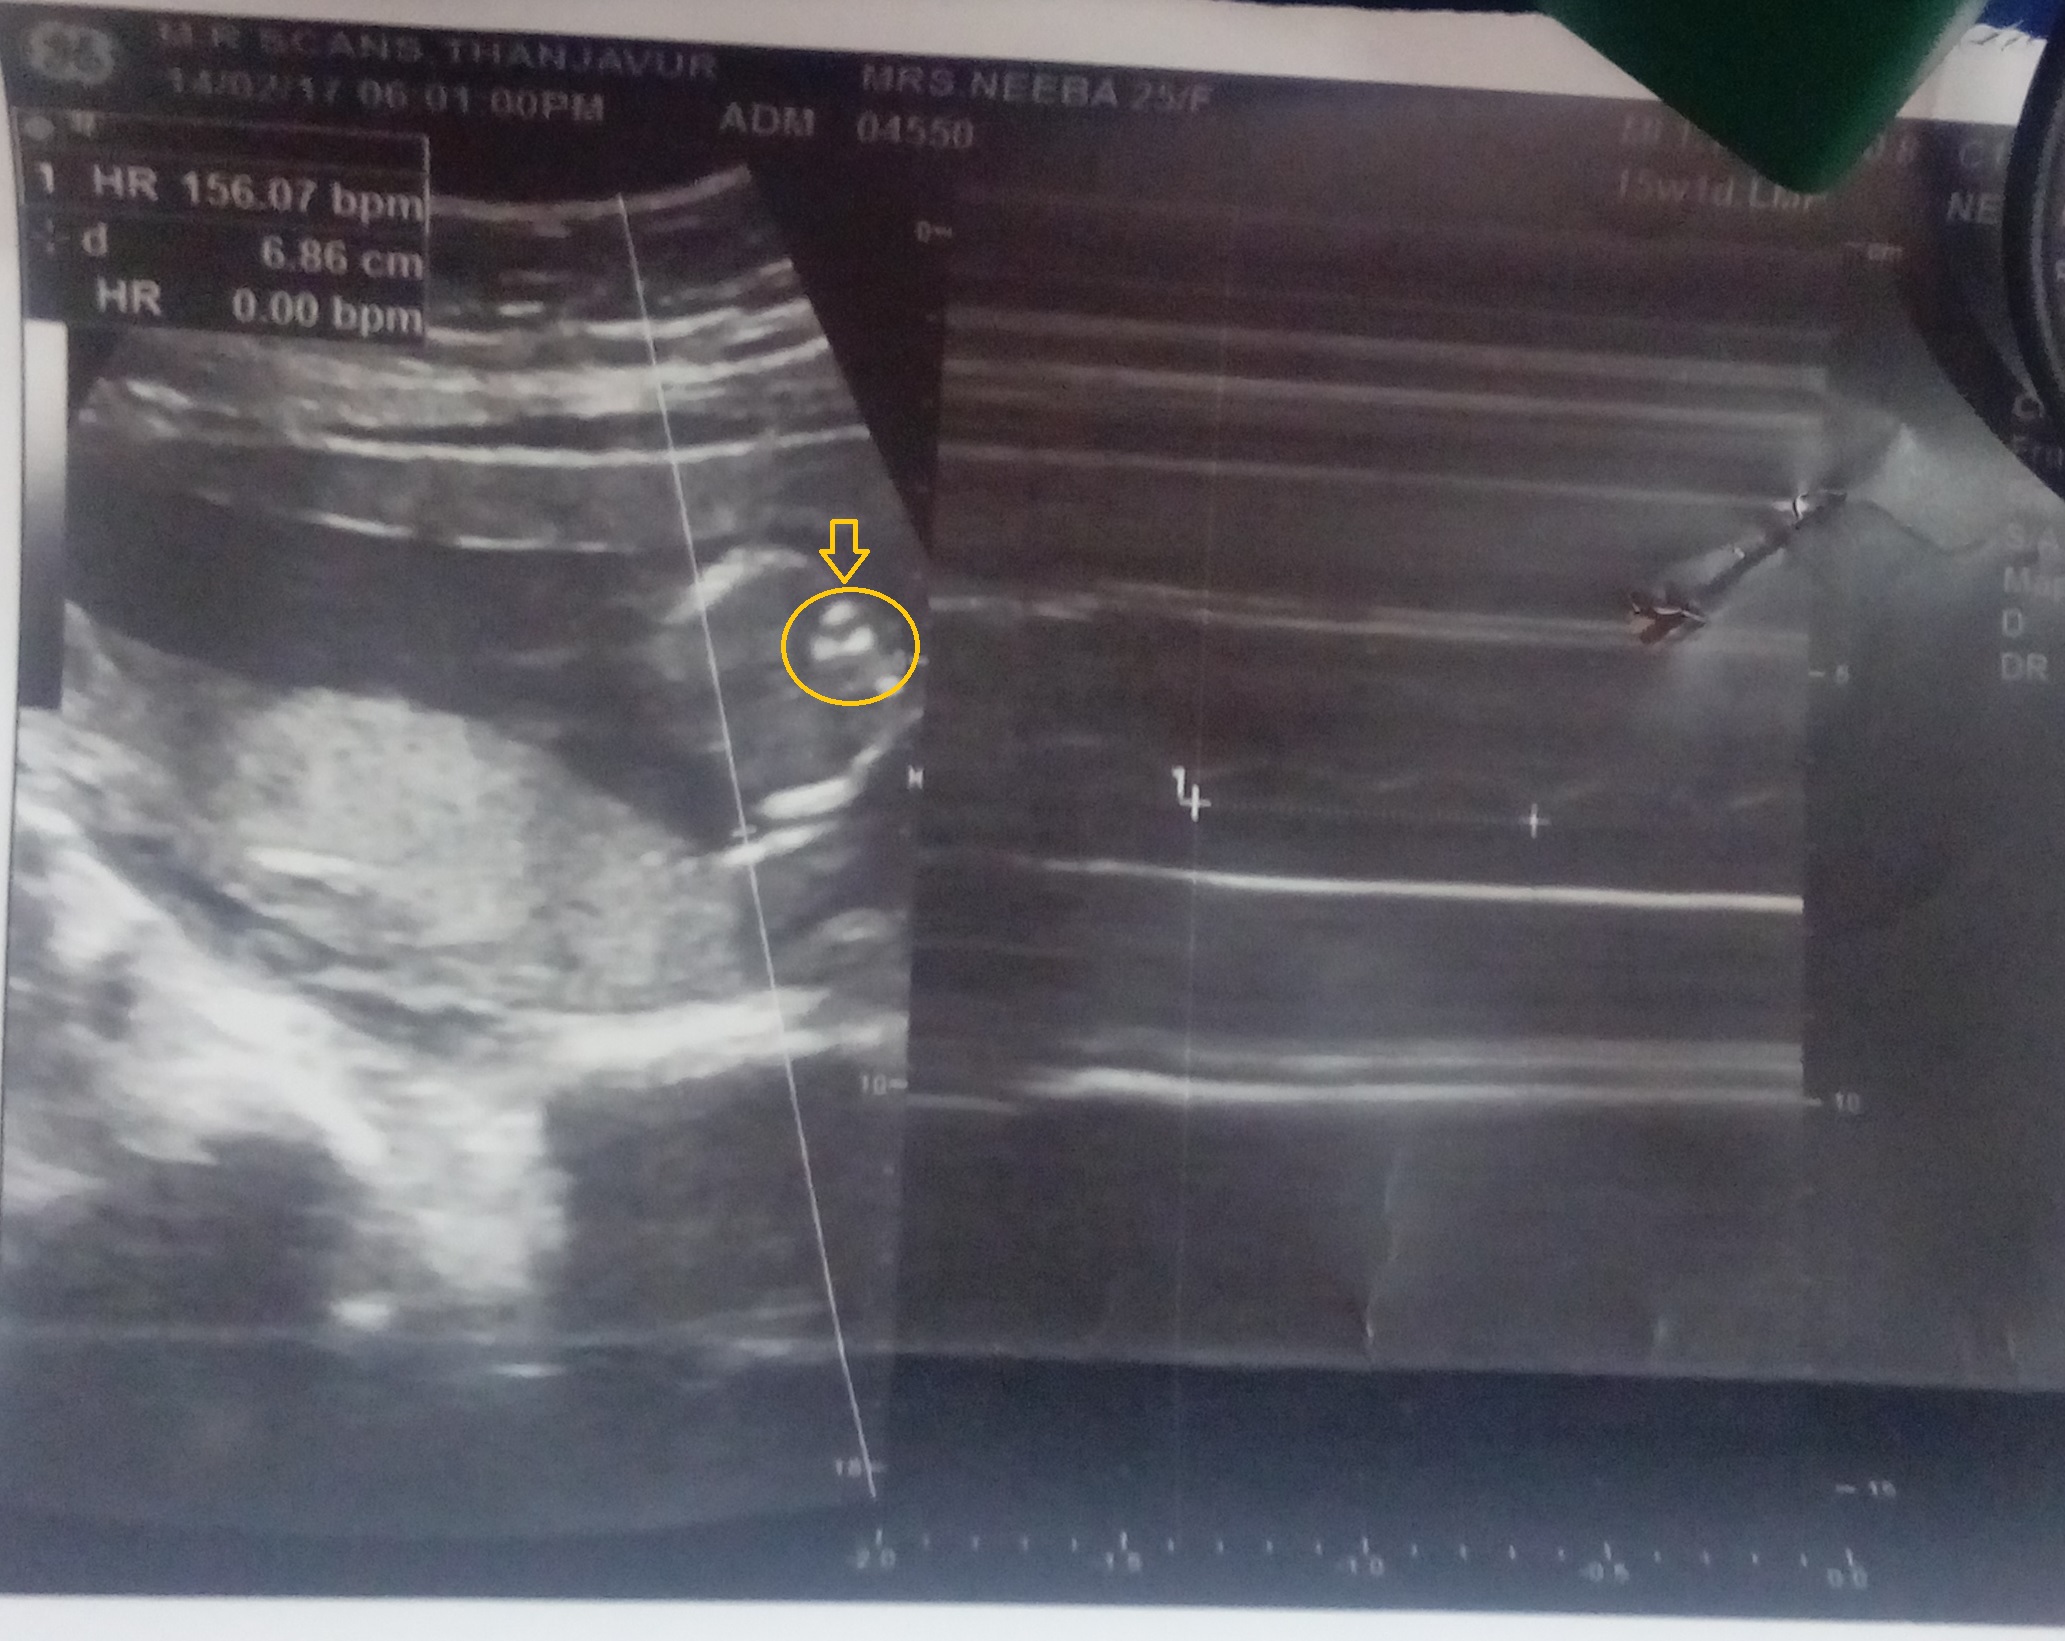

Attachment 35437

im very much confusedAttachment 35438, i could see both nubs